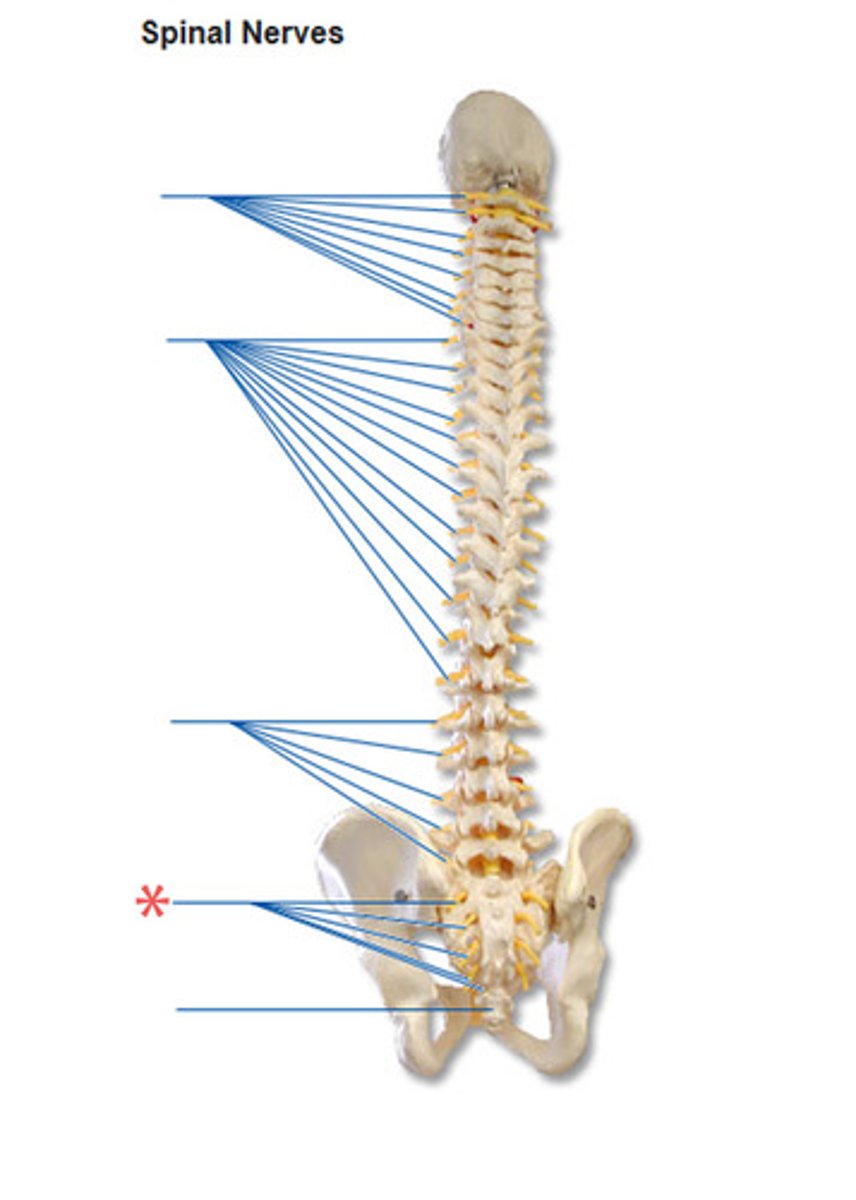

spinal nerves

carry impulses to and from the spinal cord

spinal nerves

intervertebral foramen

intervertebral foramen (articulated vertebral column)